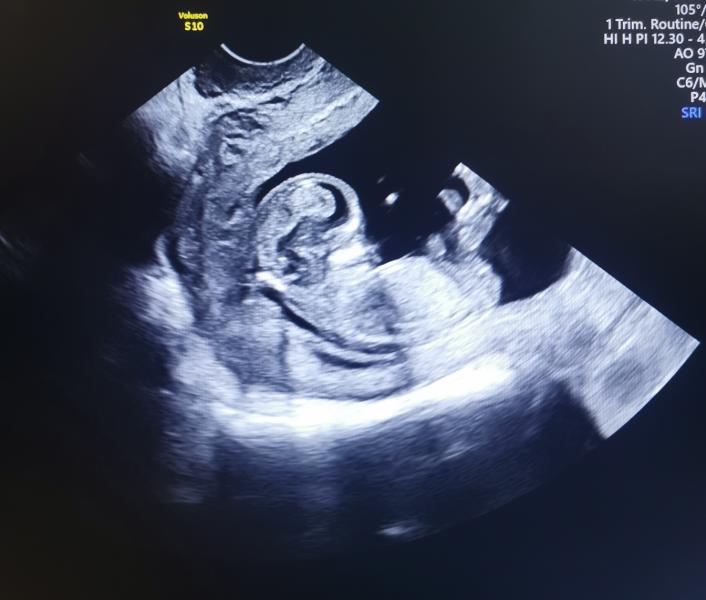

Первый скрининг пройден, ждём результаты 🤞

По узи с малышом все в порядке, да?

В 10 недель был уже тааакооой крепыш))

По анатомии плода, по каждому органу в заключение написано: патологии не выявлено)

Останется дождаться результатов со сдачи крови)

А носовую кость посмотрели? Что-то не видно в заключении